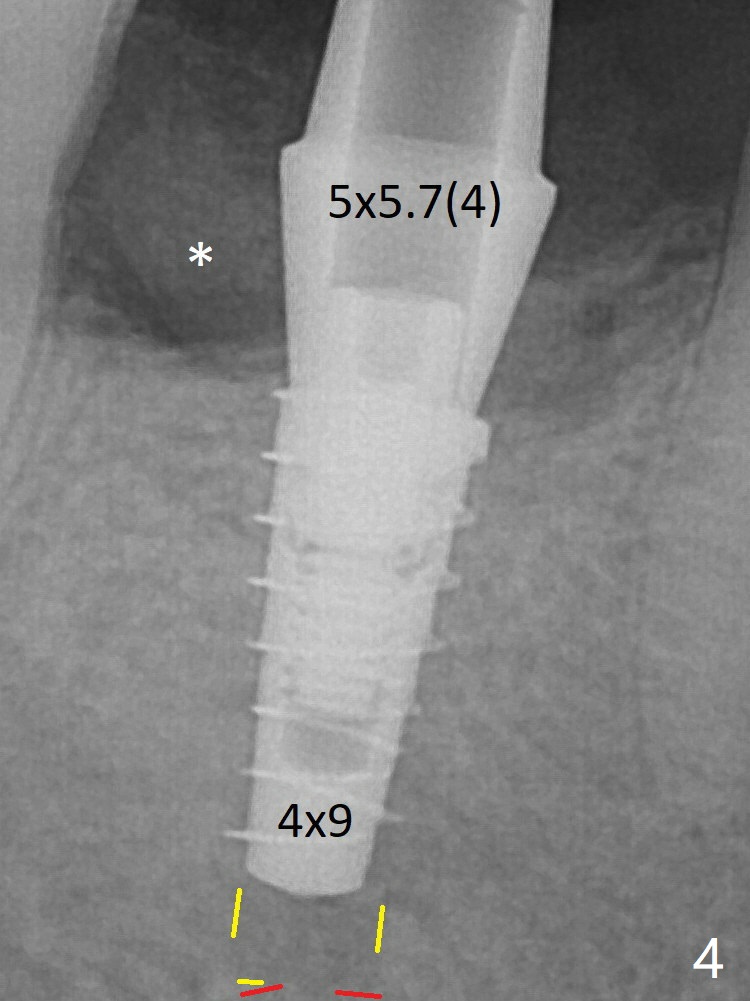

For safety, a 4x9 mm IBS implant is placed with insertion torque 40 Ncm; a 5x5.7(4) mm abutment is immediately placed for an immediate provisional to cover the large socket and keep Vera graft in place (Fig.4 *). Yellow dashed line: apical osteotomy; red dashed line: Mental Loop. Impression is taken nearly 3 months postop (Fig.6).